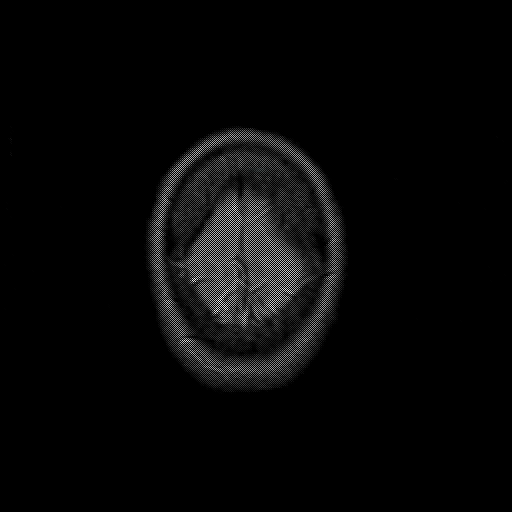

overlay : Slice 49

Slice 49

MRCBFCBF with

T1PDT2T1PDT2